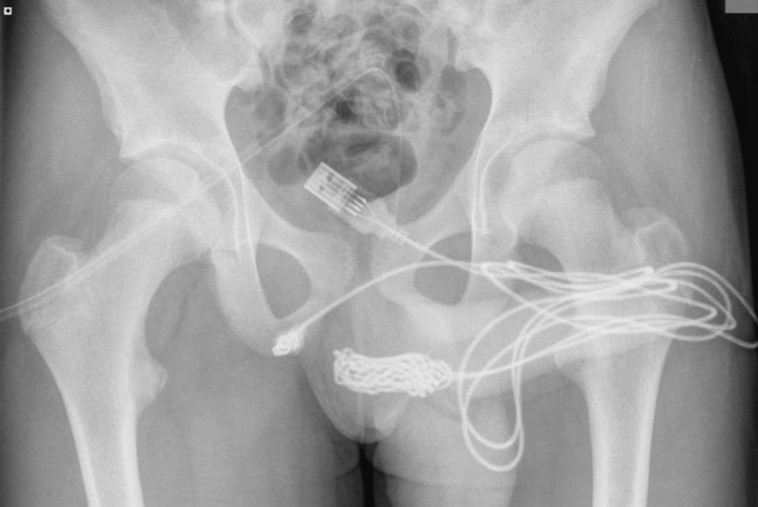

הוא לא שמע שאסור לעשות ניסויים בבני אדם? נער מתבגר נאלץ לעבור ניתוח לאחר שתקע כבל USB באיבר מינו במהלך "ניסוי מיני", בו החדיר את החוט לצינורית השופכה שלו.

על פי הדיווחים, הילד בן ה-15 ניסה למדוד את החלק הפנימי של איבר המין באמצעות כבר ה-USB במסגרת "ניסויים". אך הגוף הזר נותר עמוק בפנים והפך לבלתי ניתן להסרה.

הכבל ככל הנראה נקשר והסתבך והצעיר גילה שכשהוא מטיל את מימיו, דם יורד יחד עם השתן. בסופו של דבר, הוא סיפר לאמו ש"משהו קרה" והיא מיהרה עמו לבית החולים, שם הוא התוודה כי החדיר את כבל ה-USB בכוונה - אך לא לפני שהאם המודאגת יצאה מחדר הרופא, כך לפי הדיווחים.

בדו"ח האורולוגי שנכתב על ידי הרופאים, צוין: "התברר כי שתי היציאות הדיסטליות של כבל ה-USB בולטות מצינורית השופכה החיצוני, בעוד שחלקו האמצעי של החוט נשאר בתוך השופכה. המטופל הצעיר בריא ללא היסטוריה של הפרעות נפשיות".

הצוות הרפואי ניסה להסיר את הכבל עם מלקחיים ומוט מתכת, אך ללא הועיל. הצעיר נאלץ לעבור ניתוח והרופאים ביצעו חתך בין איבן המין לפי הטבעת שלו, וזאת כדי להצליח להגיע לכבל. אחד המנתחים הסביר: "בוצע חתך אורכי מעל הגוף הזר וחדירה זהירה דרך רקמות עמוקות יותר תוך פיצול שריר הבולבוספוגיוס. שתי קצוות החוט נשלפו בהצלחה דרך צינורית השופכה".

הצעיר החלים במהרה ושוחרר כשמחובר לו קתטר אשר הוסר רק כשבועיים לאחר מכן. בן ה-15 נאלץ להגיע לפגישות מעקב במחלקה האורולוגית ונמסר לו כי החדרת עצמים זרים לשופכה עלולה לגרום לכאבים בעת מתן שתן, דם בשתן, זקפה כואבת ואצירת שתן.